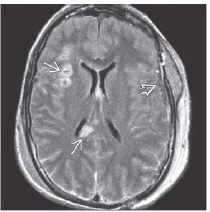

What sequence?

What is shown?

FLAIR scan in a patient 2 days after closed head trauma shows a small hypodense SDH and multiple

axonal injuries